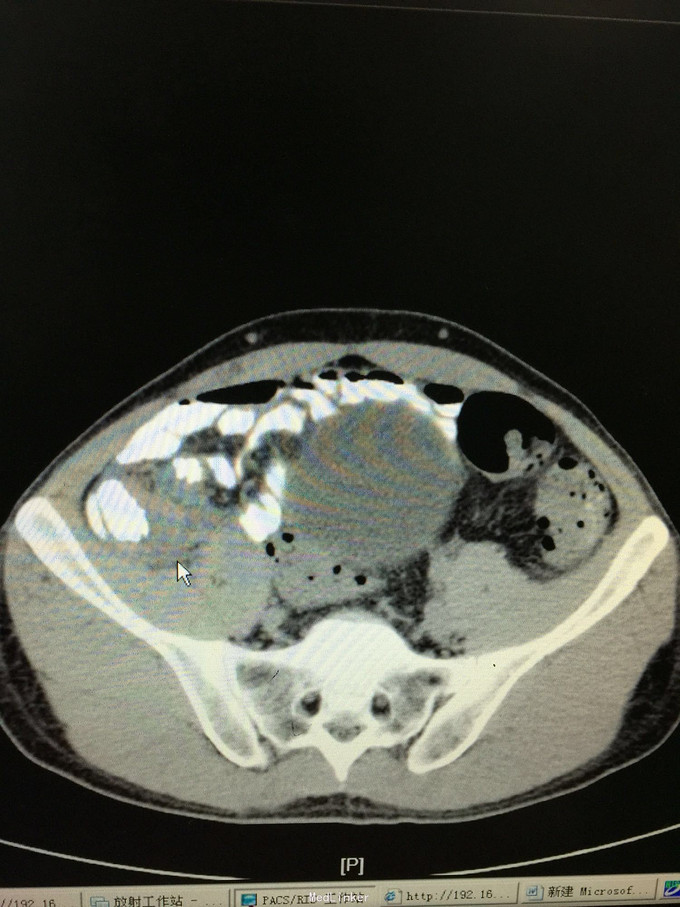

42岁男患,转移性右下腹痛5天为主诉入院。 患者5天前无明显诱因出现中上腹部疼痛,继而转移为右下腹部疼痛,呈持续性绞痛,发热最高体温38.4摄氏度,无恶心呕吐,无寒战,排气排便正常,自行给予口服抗炎药物治疗后发热缓解,腹部疼痛症状缓解不明显,并有加重趋势来诊。门诊查彩超示阑尾炎伴周围脓肿,并收入院治疗。既往发现乙型肝炎肝硬化3年。家族遗传性乙肝

查体:各生命体征正常,心肺无异常,腹部查体:腹平坦,未见腹壁静脉曲张,腹软,未见胃肠型及蠕动波,右下腹可触及一质韧包块,大小约5✖️3cm,界限欠清,活动度一般,右下腹压痛阳性,反跳痛弱阳性,无肌紧张,以麦氏点压痛为重。 辅助检查:详见图片

诊断:急性阑尾炎伴阑尾周围脓肿,乙肝肝硬化 处理:患者入院后经查无腹膜炎体征,经上级医师查看后指示患者阑尾炎伴周围脓肿形成,存在手术相对禁忌,无手术绝对指证,建议给予积极抗炎对症治疗,患者肝炎肝硬化,注意各理化指标变化,积极复查。